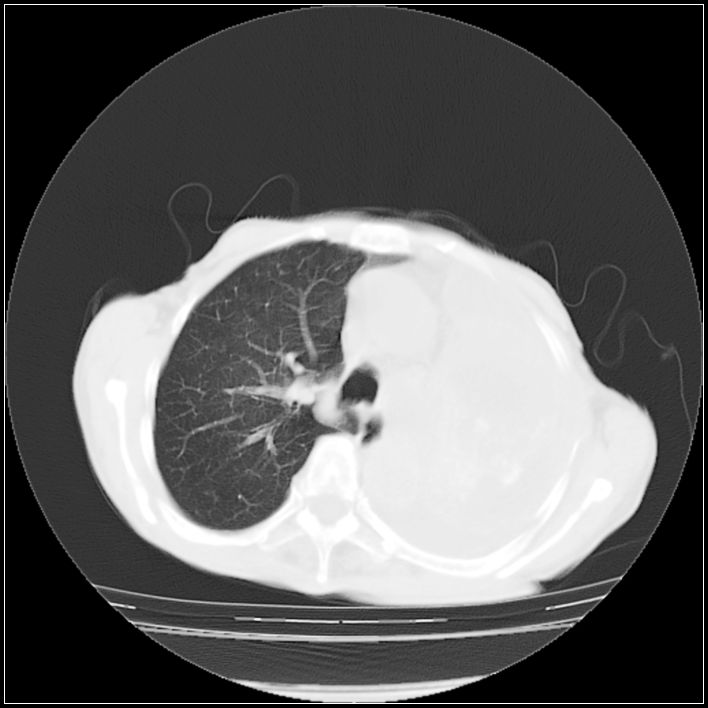

以下是引用ydx_74在2008-5-31 16:08:00的发言:[br]中心性肺癌并左侧肺不张、胸水。

以下是引用影象小辈在2008-5-31 16:25:00的发言:[br]左侧胸腔团状不规则致密影,界欠规整,密度不均匀,其内可见更低密度影及高密度影,并可见包裹性胸腔积液 考虑为1.畸胎瘤 2.肺癌